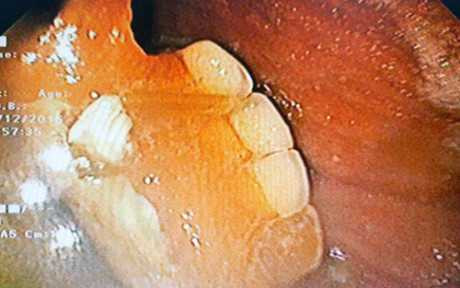

Khung hàm với 3 răng giả được phát hiện trong dạ dày bà D. (Ảnh: BVCC)

Khung hàm với 3 răng giả có kích thước 2cm x 3cm nằm lẫn cùng với thức ăn ở bờ cong lớn dạ dày. Ngay sau đó, các bác sĩ đã dùng kìm tiến hành gắp dị vật ra.